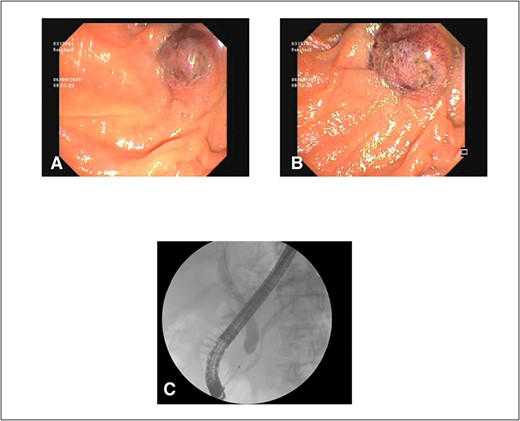

Histopathology of the ampullary lesions collected at ERCP showed evidence of malignant large cell tumour with diffuse and focally nested proliferation of epithelioid-shaped cells positive for Melan-A and Sox10 on immunohistochemistry, which was consistent with malignant melanoma (Fig. 4). Additionally. tumour cells were positive for BRAF v600 mutations; thus, this patient would have been eligible for BRAF inhibitors.

(A) H&E ×400 slide showing pigmented melanoma cells with surrounding normal tissue; (B) H&E ×40 slide with normal ampulla tissue on far left and tumour in centre; (C) MelanA ×200 stain with melanoma; and adjacent normal ampullary tissue on the left; cytoplasmic expression of MelanA/MART1 highlights how the melanocytes are obscured by a dense lymphocytic infiltrate than in the conventional H&E slide; (D) Sox10 stain ×200 similarly showing discoloration by malignant melanoma cells with surrounding normal ampullary tissue.